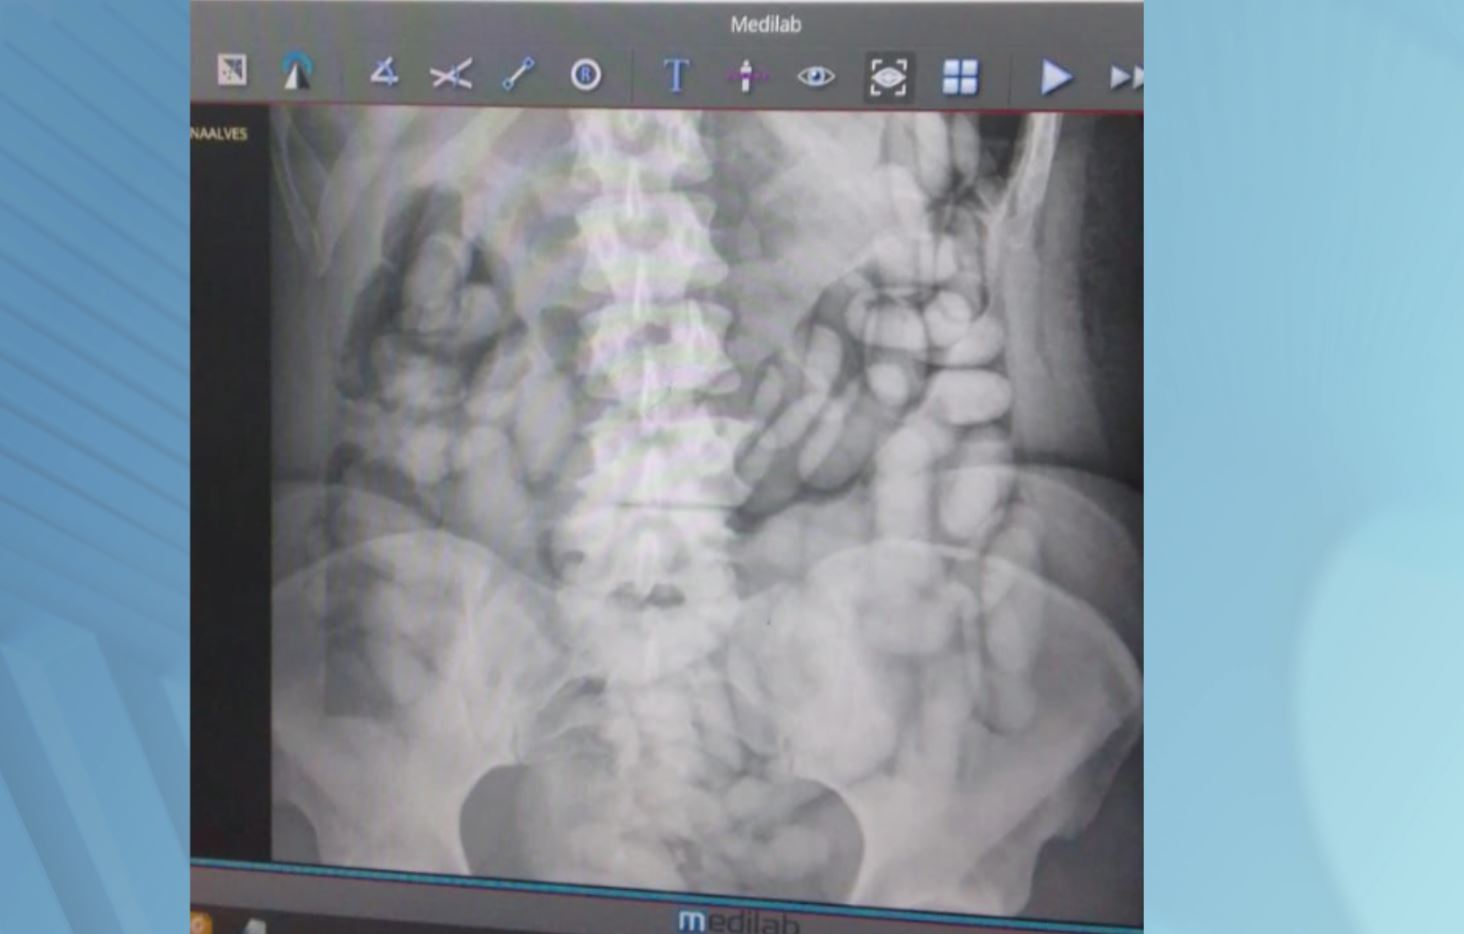

A Polícia Federal e a Receita Federal prenderam em flagrante uma passageira brasileira, de 37 anos, que tentou embarcar em um voo para Paris, com drogas no estômago.

Segundo a Polícia, ao ser levada ao atendimento médico foram expelidas 29 cápsulas da droga.

A passageira foi internada até eliminar todas as cápsulas, porém ainda não se sabe quantas foram ingeridas ao todo.